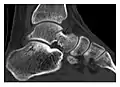

The greater tuberosity of the humerus is also an illustrative location of occult fractures. The osseous injury may follow seizures, glenohumeral dislocation, forced abduction, or direct impaction. They are commonly discovered on MRI in symptomatic patients with suspicion of rotator cuff tear. Coronal images are best suited for detection. They appear as crescentic oblique lines surrounded by a bone marrow edema pattern (Figure 5). The rotator cuff must be inspected since associated ligamentous lesions are common. In the ankle, malleoli and tarsal bones should be checked carefully for any cortical disruptions and radiolucent lines that may reveal a fracture. Awareness of the exact location of the pain will help direct the attention of the interpreter when searching for very subtle signs of fracture (Figure 6).[1]

- a

- b

Figure 6: Subtle anterior talar fracture in a 39-year-old man presenting with ankle pain after a fall. (a) Anteroposterior radiograph shows a subtle oblique radiolucent line through the talus (white arrows). (b) Sagittal CT reformation confirms the presence of an anterior talar fracture with cortical offset (black arrow). Avulsion fractures, which consist of a detached bone fragment resulting from a ligament or tendon pulling away from the bone, may also present with subtle radiographic signs. Tiny osseous fragments near the presumed attachment site of a ligament suggest this diagnosis. Common sites are the lateral tibial plateau (the Segond fracture), the spinal tuberosity of the tibia resulting from anterior cruciate ligament avulsion, and the ischial tuberosity.[1]